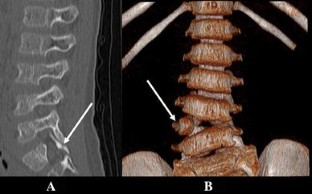

Fig. 1